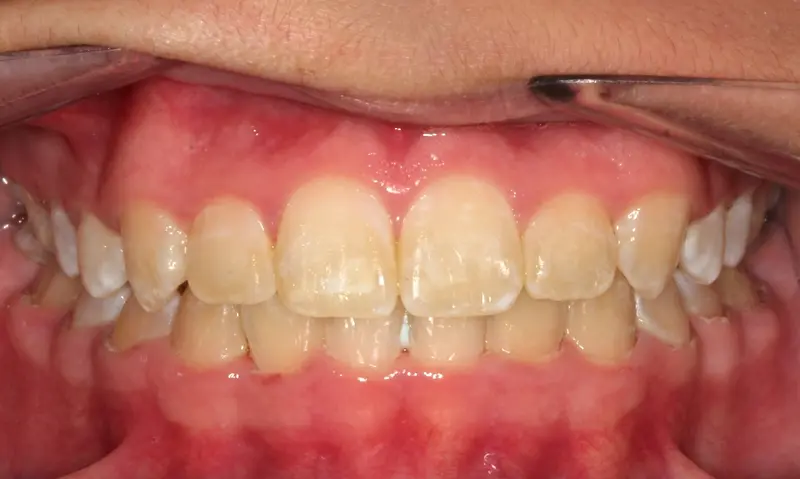

After treatment: Complex Bite Correction

After

Before treatment: Complex Bite Correction

Before

Anterior Open Bite with Class III tendency (Underbite). The front teeth did not touch, making chewing difficult and placing excessive force on the back teeth.

Using Invisalign with "SmartForce" attachments, we intruded the posterior teeth (molars) to close the bite at the front. We simultaneously corrected the underbite relationship using precision-cut elastics, achieving full function without surgery.